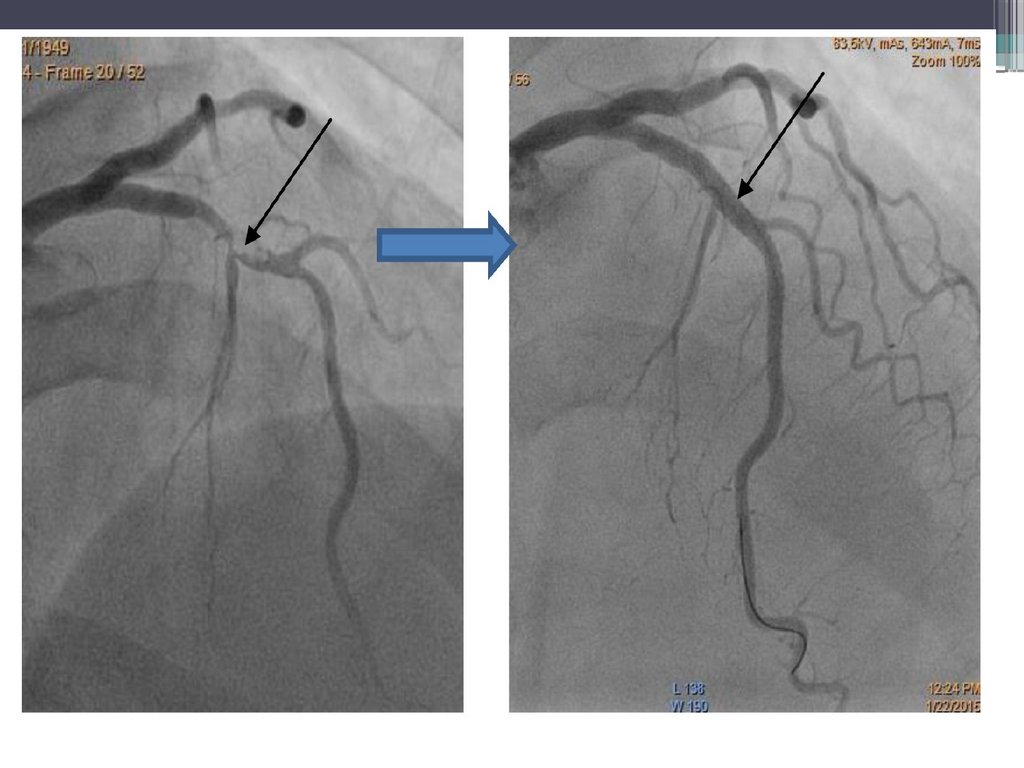

ОКС без подъема сегмента ST

Неокклюзирующий(зачастую реканализированный тромб в просвете крупной

коронарной артерии;

Окклюзия коронарной артерии мелкого калибра (1-2 мм диаметра);

Неокклюзирующий

тромб

16.

17.

18.

19.